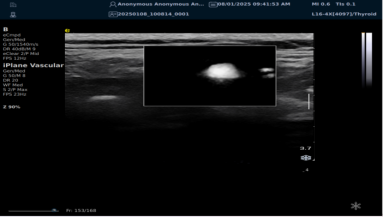

iPlane Vascular 平面波超微细血流显像技术

iPlane Vascular 技术借助 OmniSound?平面波和 3D 壁滤波技术突破,提升超声多普勒分辨率并具备定量测量能力。优势如下:

image.png

? 显著提高对低速血流的敏感度,实现高分辨率、高帧频实时微血流成像(分辨率 30 微米、帧频 150 /s),动态显示斑块内新生血管血流。

? 基于多普勒原理进行频谱测量与 VI 指数计算,定量评估斑块内新生血管。

? 成像质量接近造影效果且无需造影剂,无创简便,增强诊断准确性,适用于细微血流变化场景。